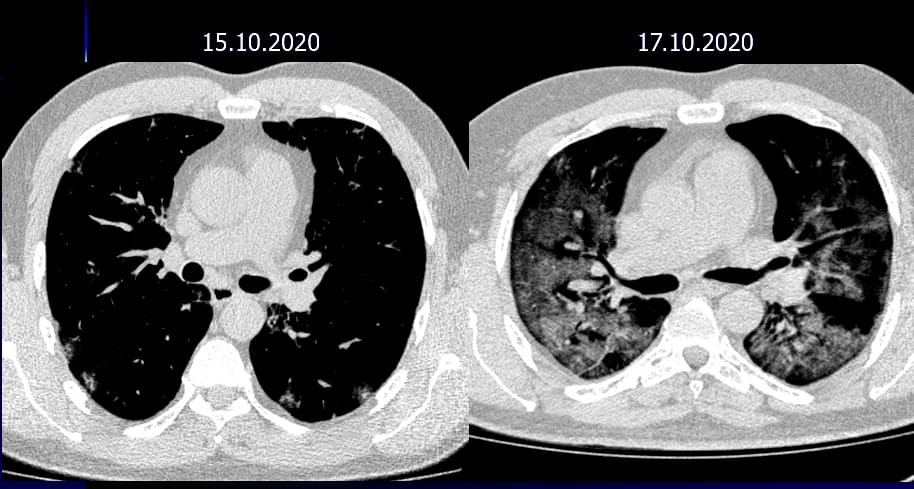

Течение может быть настолько агрессивным, что от первых симптомов, первых очажков матового стекла до диффузного тотального поражения могут пройти всего лишь десятки часов. Если не среагировать на ситуацию вовремя, помочь больным уже не можем.